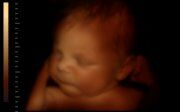

Обсудив, что же такое измерения - можно теперь понять, что такое 4D УЗИ. Кстати можете в Москве воспользоваться удобным сервисом по поиску. На самом деле данная технология объединяет все предыдущие модернизации УЗИ, которые мы уже обсудили вначале статьи. Суть в том, что мы получаем трёхмерное цветное изображение в режиме реального времени. Именно таким образом можно оценивать все органы человека и плода у матери. Таким образом современные технологии не просто появляются где-то, а вот они уже в Москве во многих клиниках. Просто звоните и хоть завтра обученные специалисты проведут самую детальную диагностику в современном мире. Как говориться: "любой каприз за Ваши деньги", так что и здесь у Вас не возникнет проблем.